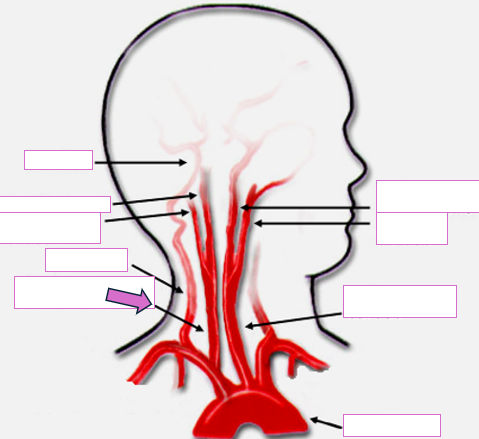

Based on the indicated area, identify this vessel

Brachiocephalic/innominate artery

Right subclavian artery

Right vertebral artery

Right carotid artery

Left carotid artery

Left vertebral artery

Left subclavian artery

Aortic arch